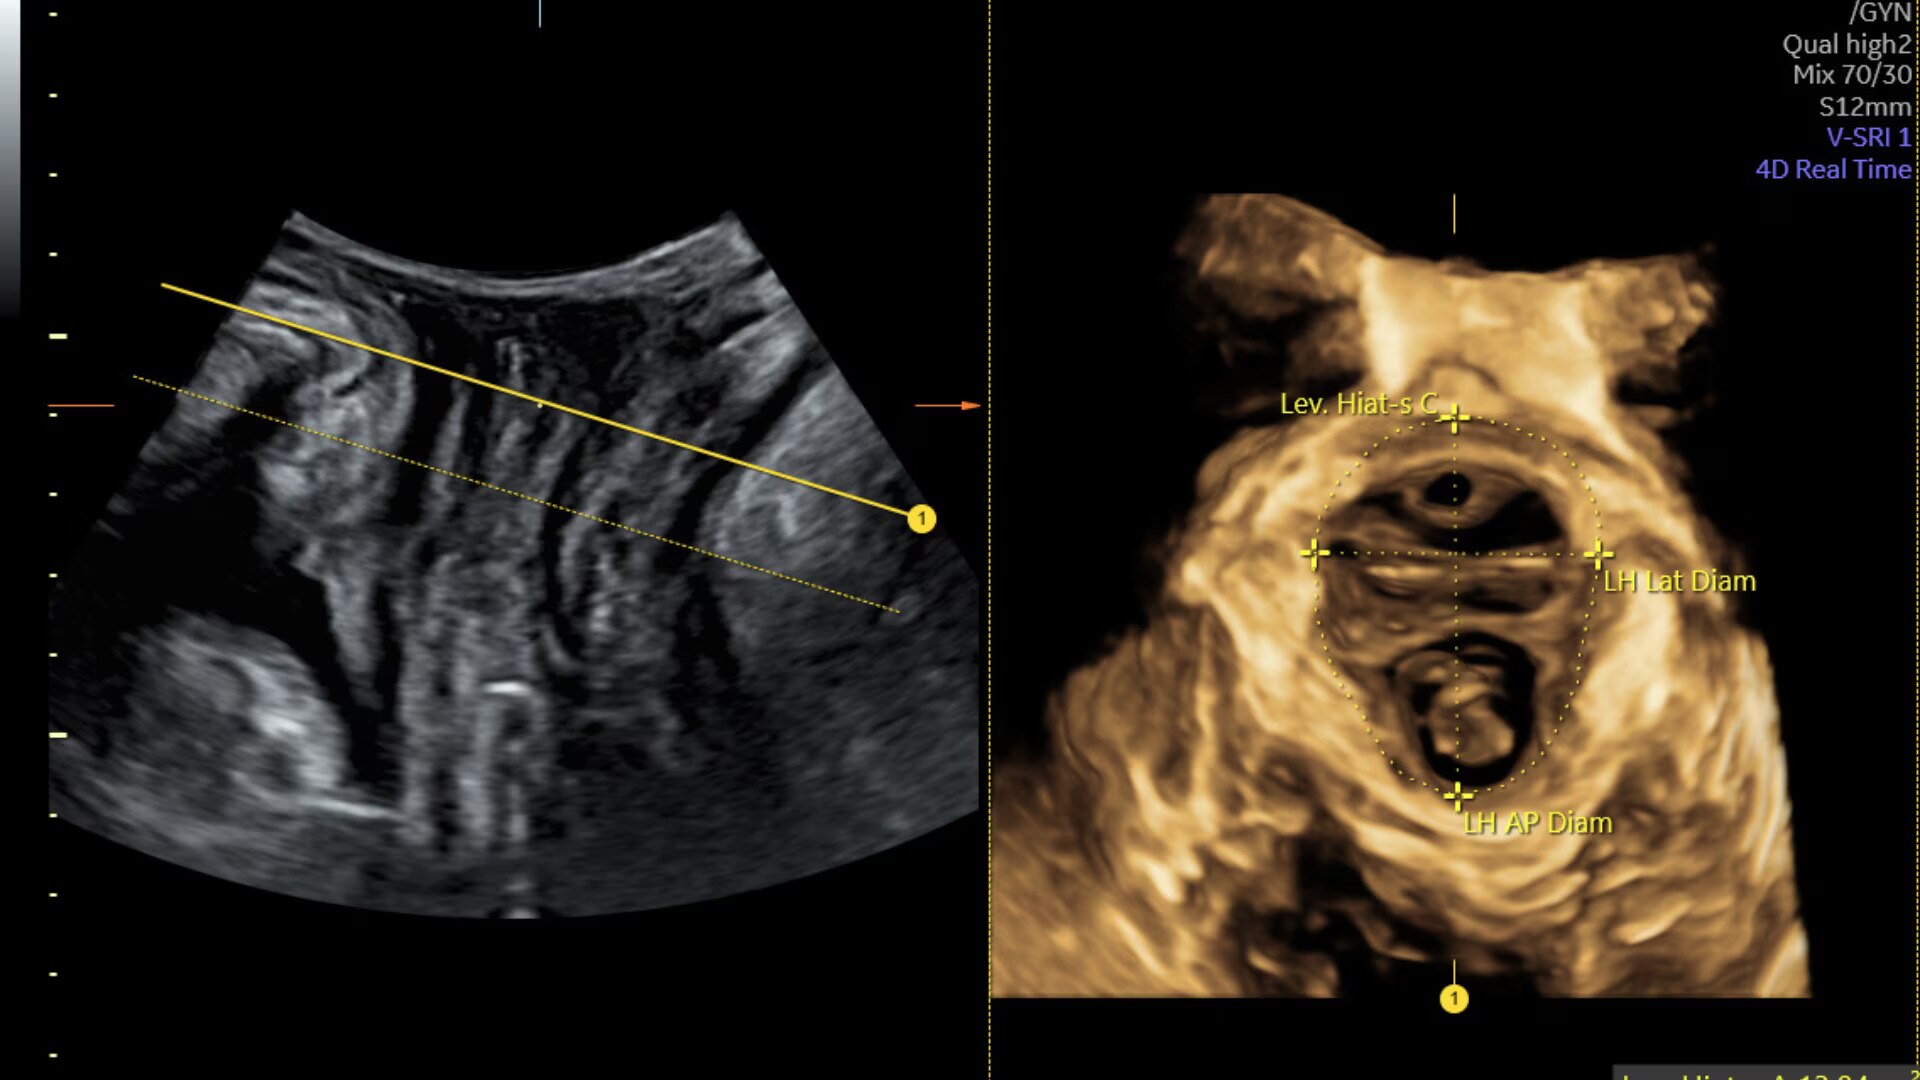

Sonopelvicfloor

Assess pelvic floor anatomy using guided workflow & AI

Using a guided workflow and AI, SonoPelvicFloor:

• removed exam complexity by automating plane alignment and measurements

• can reduce keystrokes by up to 75% and offer users a time savings of up to 80%